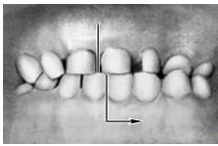

Прикус (occlusio) — соотношение зубных рядов при наиболее плотном смыкании зубов. Смыкание зубов верхней и нижней челюстей при различных движениях последней называется окклюзией. Откусывание и прожевывание пищи сопровождаются различными видами окклюзий. Откусывание осуществляется при передней (сагиттальной) окклюзии, когда смыкаются передние зубы, а боковые разобщаются (между ними появляется просвет). При жевательных движениях возникают боковые (трансверзальные) правая и левая окклюзии. Исходным и заключительным положением для всех жевательных движений нижней челюсти являются центральная (вертикальная) окклюзия, при которой линия, проходящая между центральными резцами обоих зубных рядов, совпадает со срединной линией лица.

Различают несколько вариантов нормального П. (ортогнатический, прогенический, прямой, бипрогнатический). Они характеризуются смыканием зубных рядов на всем протяжении и отличаются друг от друга лишь особенностями смыкания функционально ориентированных групп зубов, в частности передних. Эталонным принято считать ортогнатический прикус (рис. 5, а), при котором верхний зубной ряд на всем протяжении перекрывает нижний, а во фронтальном участке верхние резцы перекрывают нижние не более чем на 1 /3 коронковой части зуба; между резцами верхней и нижней челюстей имеется режуще-бугорковый контакт. Прогенический прикус (рис. 5, б) отличается умеренным выстоянием нижнего зубного ряда. Прямой прикус (рис. 5, в) характеризуется тем, что верхние резцы не перекрывают нижние, а смыкаются режущими краями. При бипрогнатическом прикусе (рис. 5, г) верхние и нижние резцы наклонены в сторону преддверия рта, но между ними сохранен режуще-бугорковый контакт. Для всех вариантов нормального прикуса обязательным условием является нормальное функционирование зубочелюстной системы.